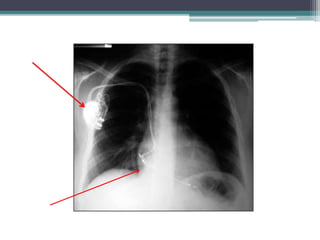

Incidência: PA

Orientação: Direita e esquerda

Rotação:extremidade das clavículas e sem um processo

espinhoso

Penetração: Muito penetrada

Diafragma: Seio Costofrênico

Coração : área Cardíaca aumentada e duplo contorno

cardíaco.